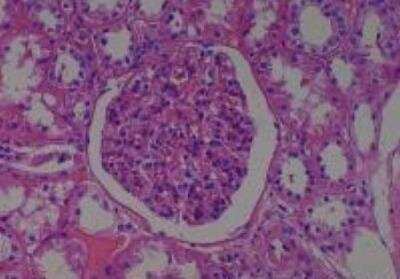

Scientific Data Images for Human Multi Tissue MicroArray (Normal Adjacent)

Hematoxylin & Eosin Stain: Human Common Tissue MicroArray (Normal Adjacent) [NBP2-30215] - 01. Stomach

Hematoxylin & Eosin Stain: Human Common Tissue MicroArray (Normal Adjacent) [NBP2-30215] - 102. Stomach

Hematoxylin & Eosin Stain: Human Common Tissue MicroArray (Normal Adjacent) [NBP2-30215] - 103. Stomach